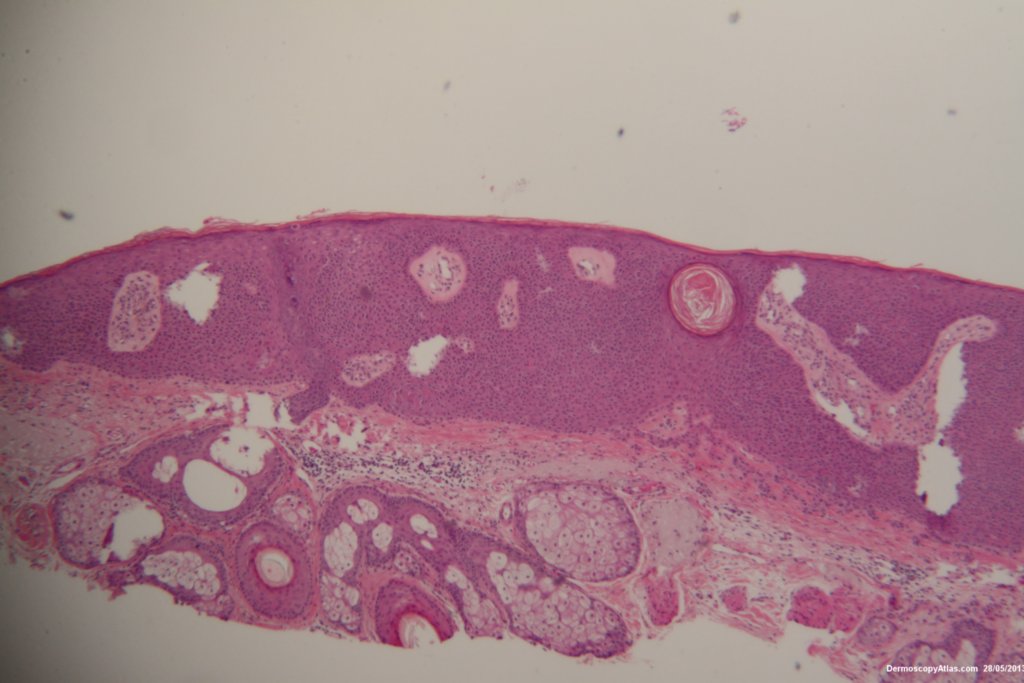

Diagnosis: Seborrhoeic keratosis

This was a case of scalp pigmentation looking like a lentigo maligna but actually being a seborrhoeic keratosis. The pigmentation is structureless with some milia. The area was shaved to confirm the diagnosis